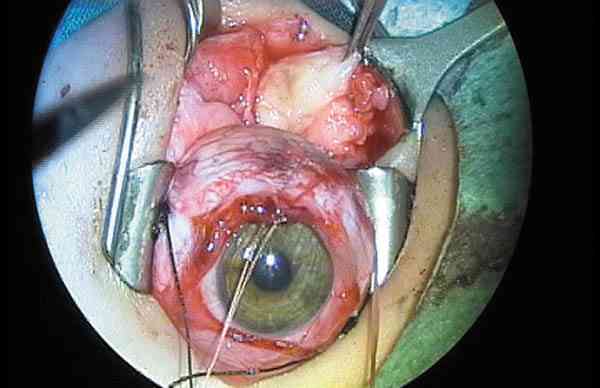

Figura 35. La extirpación de rabdomiosarcomas utilizando la

crioterapia como elemento de tracción es una práctica habitual en la cirugía

de la órbita en la infancia.

La biopsia intraoperatoria permite establecer el diagnóstico. Se necesita

bastante material para congelación, microscopia óptica, electrónica e

inmunohistoquímica. La cirugía pocas veces reseca todo el tumor ya que es

friable y casi nunca pequeño y circunscrito. La extracción con crioterapia,

sin dañar zonas vitales y ser meticuloso es fundamental. Saber concluir la

cirugía si las adherencias e infiltraciones hacen peligrar la estructura

orbitaria es de sentido común pero perjudica el ego de los cirujanos que

requieren resultados espectaculares (135,140,143).